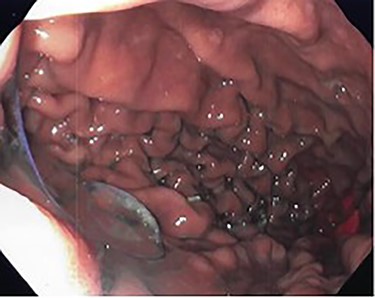

Preoperative endoscopy (post gastroplasty) showing the body of the stomach without restrictive sleeve appearance.

Patient subsequently underwent a robotically assisted laparoscopic paraesophageal hernia repair with mesh, partial gastrectomy with removal of gastric foreign bodies, and flexible endoscopy. Intraoperatively via initial laparoscopic approach, there was only noted to be small dimples along the greater gastric curve without any noticeable plication (Fig. 3). The stomach was twisted up into the hiatal hernia. Multiple permanent sutures with T-fasteners were seen on endoscopy, and attempts were made to remove these endoscopically without success. These sutures were not of full thickness, so a gastrotomy was made to remove them. Partial gastrectomy was performed, including the fundus. The diaphragm was repaired with interrupted silk sutures and reinforced with a bioabsorbable mesh. The patient recovered well and was discharged home on postoperative day two tolerating a diet. She was seen at follow-up with complete resolution of her preoperative symptoms.